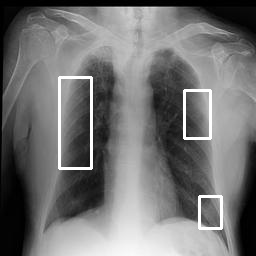

COVID-19 CXR Analyzer - Under Construction

Image for analysis